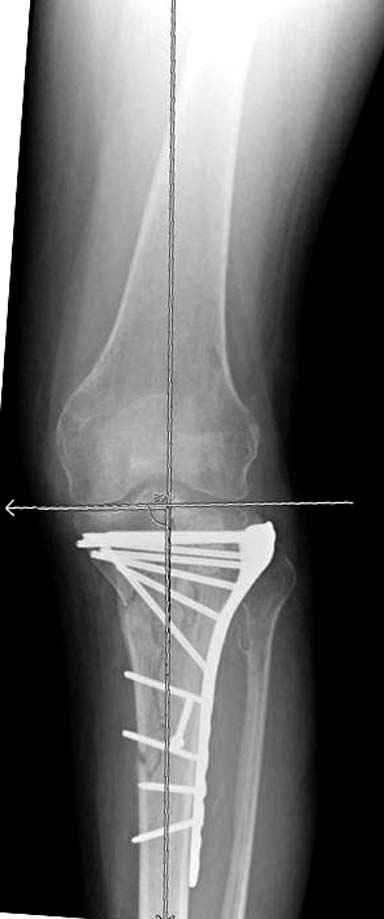

А нет ощущения, что плато "завалено" на варус?

293.jpg

21KB (22230 bytes)

Только вот линией вы вальгус показываете (норма)

Коллега, а нет ли снимков здоровой ноги, чтобы сравнить оси, если уж наши мнения разошлись?

Конечно, при таком повреждении всегда сложно выставить ось голени, знаю по собственному опыту, но все же?

Отдельные переломы тибиал плато и перелом проксимальной трети большеберцовой кости отличаются от переломов тибиал плато с вовлечением диафиза. Здесь перелом тибиал плато типа Schatzker VI, полученный в результате высокоэнергетической травмы. Перелом метафиза образовал отрыв суставной поверхности от диафиза с вовлечением медиального и латерального мыщелков. Двухмыщелковые переломы из-за укрочения опасны развитием компартаментального синдрома, повреждением латерального мениска и связок.

На вашем место я бы подождал с фиксацией до готовности кожных покровов, и за это время можно было подобрать соответствующий фиксатор, т.е более длинная пластина снаружи и медиальная пластина на апексе перелома как подпорка. Здесь приемлем как раз минимальный доступ.

Я думаю, что если с новыми, услышанными, например, от экспертов форума, оценками и размышлениями Вы вернётесь к изучению представленной Вами рентгенограммы, то увидите, что вы не восстановили ни плато, ни правильные осевые взаимоотношения. Вы оперировали на отёке, не в оптимальное время. Используя болты-стяжки, вы устроили то, что зачастую называют «костный сэндвич», такое сдавление кости много-много хуже для биологии, чем аккуратно введённая малоинвазивная вторая небольшая пластина с медиальной стороны. К тому же, и это чрезвычайно важно – ни пластина, ни заглублённый гвоздь не предотвращают здесь возможности развития вторичного варусного коллапса плато. А в условиях недостаточности опоры для медиальной суставной поверхности и латерально – ввиду отказа от пластики и отсутствия «рафтинга», слишком уж много «критических точек» нужно пройти данному пациенту. Я не знаю, куда это смотрят концы болтов стяжек? Или это гайки лежат внутрикостно? И прочая, прочая, прочая, что уже, впрочем, отмечено экспертами форума.